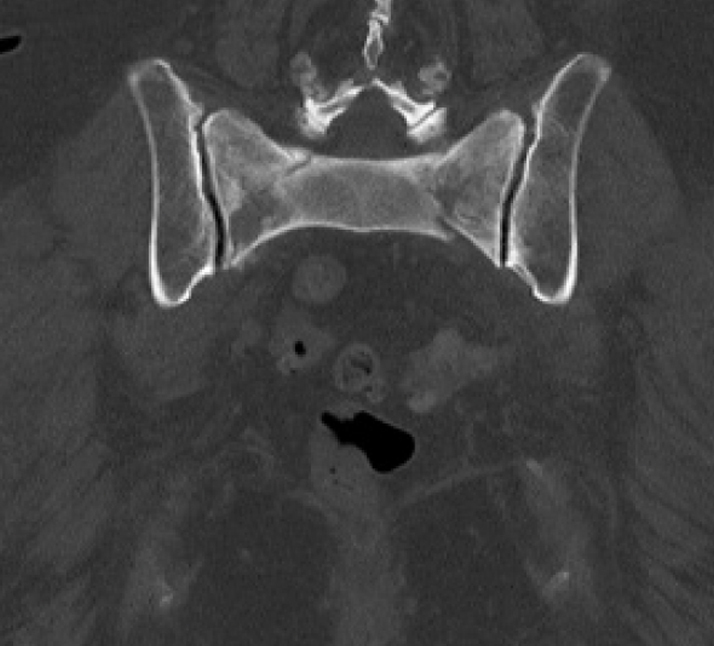

Diagnosis:

• Chronic Sacral U-type fracture with kyphotic deformity

• Anterior ring disruption

• Osteopenia